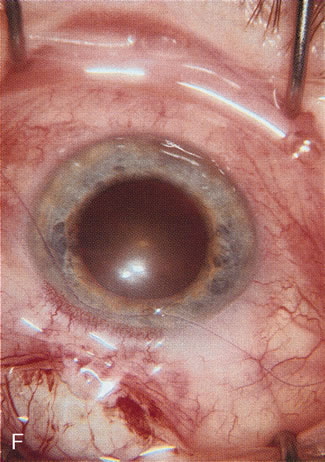

CASE 5: ANTICIPATED LENS EXTRACTION POST SUCCESSFUL TRABECULECTOMY

A patient with long-standing primary open-angle glaucoma with a successful glaucoma filtration procedure and IOP of 10 mm Hg on no antiglaucoma medications develops a significant, moderately dense nuclear sclerotic cataract. This patient is best served by small incision cataract extraction with foldable IOL implantation. Less desirable options include ECCE with IOL implant via clear cornea, temporal limbus, or inferior approach. Astigmatism, wound instability, prolonged visual recovery, visual fluctuation, exposed sutures, and bleb failure are the major drawbacks to large-incision lens extraction. Even after the surgeon has mastered large-incision clear corneal cataract extraction, long-term wound shift and astigmatism are a chronic problem (Fig. 6). Inferior cataract extraction is difficult for those not experienced with it. With the advent of small-incision phacoemulsification surgery, the surgeon is now able to use a limbus approach adjacent to the bleb or a clear corneal temporal approach. Postoperative inflammation is less with the smaller incision, and filtering blebs are more likely to survive. Patients with IOP greater than 10 mm Hg after a filtering procedure are more likely to experience permanent IOP elevation after phacoemulsification. Patients should understand that IOP elevation post cataract extraction is always an issue, even with a functioning filter.

Fig. 6. ECCE following trabeculectomy. The larger corneal incision associated with ECCE leads to a host of problems that are typically less severe with small incision cataract surgery. With improved phacoemulsification techniques, this type of incision is infrequently encountered. This bleb failed following ECCE, and topical antiglaucoma therapy was restarted. Long-term wound drift; astigmatism, and corneal decompensation are additional visual factors. However, when the nucleus is brunescent and phacoemulsification risky, surgeons with the skill to convert to ECCE through a clear corneal incision are at a significant advantage. This 11-mm free hand incision takes considerable practice and skill to master.